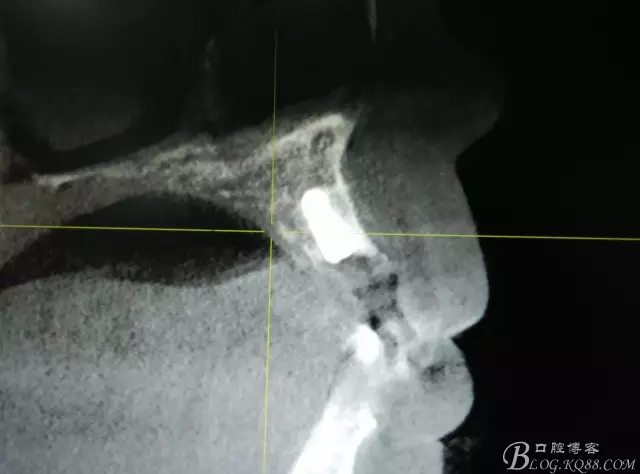

圖11.術(shù)后的CBCT檢查:

圖7.植入種植體。奧齒泰:直徑3.5mm。長度11.5mm。

圖8.植體頰側(cè)有約2mm間隙,植入bicon骨粉。